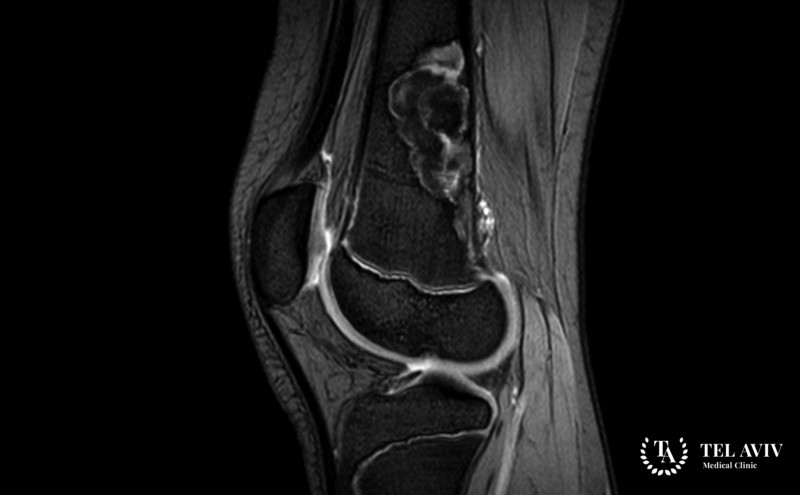

- Рентгенографический осмотр. Основной способ обнаружения хондромиксоидной фибромы. Образование имеет точные границы, поражает метафизарную зону, прорастает в эпифиз. Снимок четко отображает наличие экзофитной опухоли;

- Компьютерная томография. Применяется в качестве уточняющей методики;